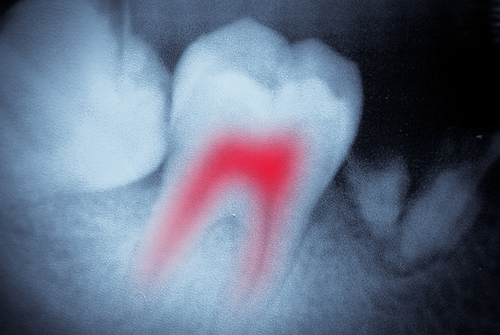

Before beginning, you’ll be numbed to avoid any discomfort. Once the medication kicks in, your dental team will get to work. First, a tiny hole is made in the infected tooth which allows access to the middle of the tooth, known as the pulp chamber. This is where the root canals are located. The root canals house pulp, nerves, and blood vessels. Your dentist will remove any and all of these materials, making your tooth no longer able to feel anything. After a thorough cleaning, the canals are sealed and the tooth is capped with a restoration.